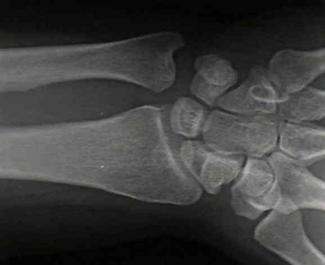

Fractura multisegmentara intertrohanteriana Fractura Salter - Harris I

Fractura Salter - Harris I Fractura Salter - Harris II

Fractura Salter - Harris III

Fractura Salter - Harris IV Fractura Salter - Harris V